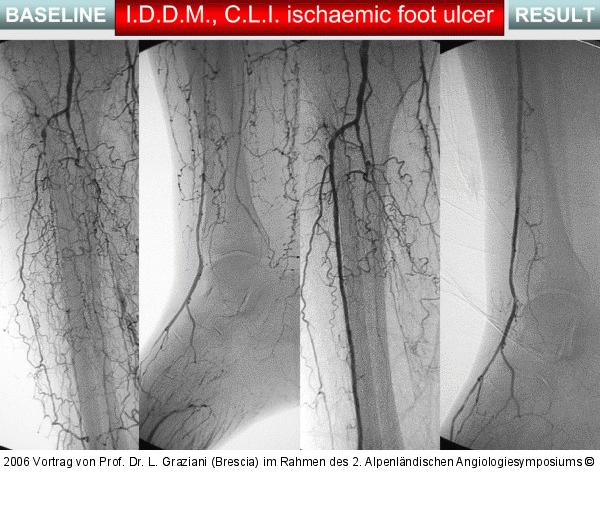

Vortrag von Prof. Dr. L. Graziani (Brescia) im Rahmen des 2. Alpenländischen Angiologiesymposiums

PTA of the foot arteries in diabetics: Extremities Extreme Angioplasty

Abbildung 41: PTA